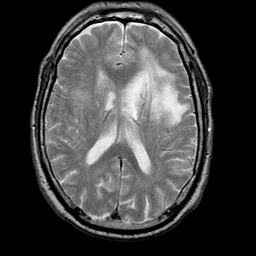

Meningioma, MR Study #1 -- Slice #11

[Home][Help][Clinical] Slice 11